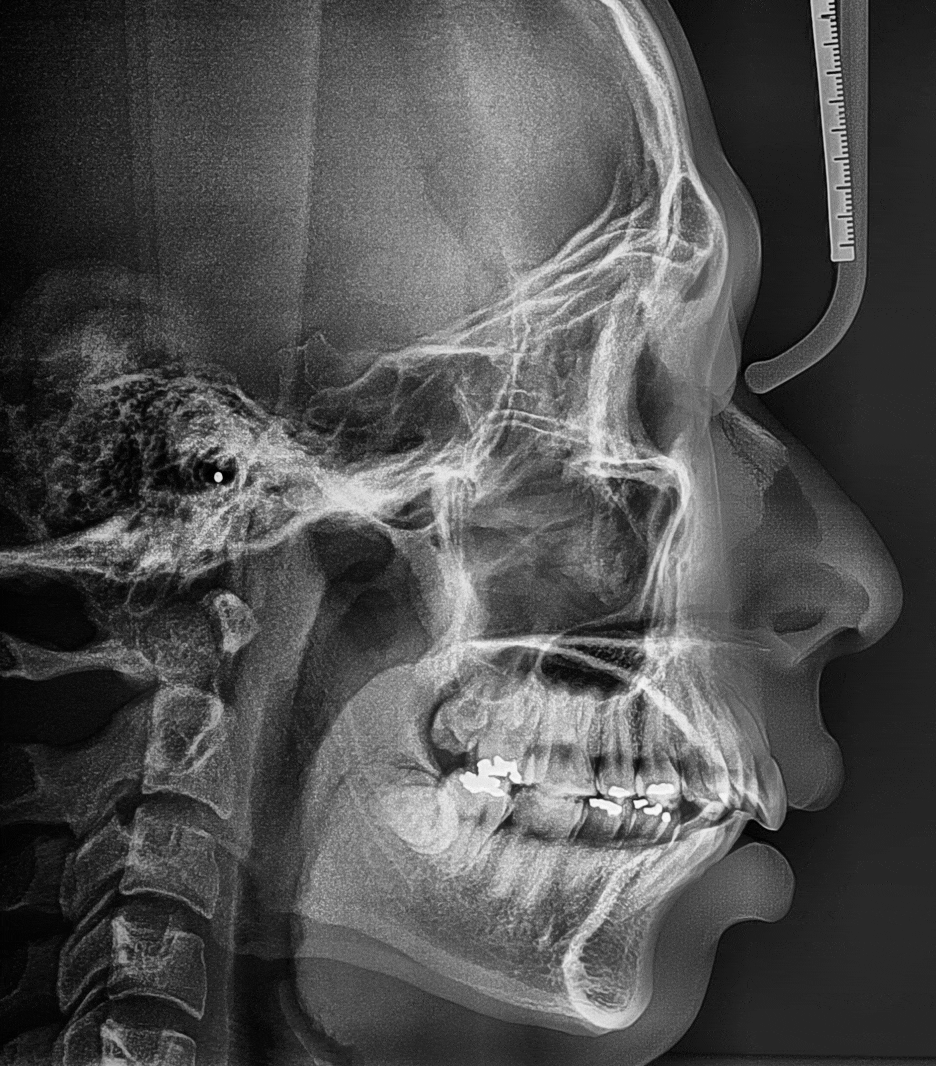

측면 사진 및 측면 두부방사선 사진을 중첩해서

보여드리는 사진입니다.

크게 2가지를 볼 수 있습니다.

- 심미선을 기준으로, 입술이 바깥쪽에 위치.

- 앞니의 치축이 앞쪽으로 많이 뻐드러져 있음.

근데, 이 분은 또 무턱의 경향이 살짝 느껴집니다.

그리고, 구치부의 교합력이 다른 사람보다

더 높으신 분이였습니다.

아마, 식습관에서 확인을 할 수 있는데

오징어나 땅콩처럼 질기거나 딱딱한 음식을

자주 드신 분들은 엑스레이에서 볼 수 있는것 처럼

사각턱의 경향 및 하악각에서 주름이 잡힌 듯한

쭈글쭈글한 형태를 확인 할 수 있습니다.

뼈가 자라는 느낌으로 볼 수 있으며,

한번 자라난 뼈는 깎지 않는 이상에는 원래대로

엑스레이 중첩 사진을 보게 되면, 수 많은

변화들이 있는 것을 한 눈에 보실 수 있습니다.

이렇게, 발치 를 하게 되면 얻을 수 있는 공간은

4~5mm 내외로 구강 내에서는 꽤 크게

느껴질 수 있는 수치 값 입니다.